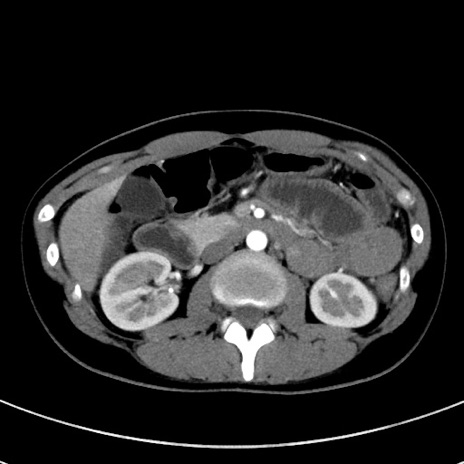

症例17(横断像)

【症例】20歳代女性

【主訴】嘔吐、下腹部痛

【現病歴】昨日夕食後に嘔吐し下腹部痛が出現。本日になっても嘔吐持続し改善しないため来院。

【身体所見】意識清明、BT 37.2℃、BP 108/67mmHg、腹部:平坦、やや硬、下腹部正中から右にかけて圧痛あり、反跳痛軽度あり、tapping pain(+)。

【データ】WBC 13600、CRP 14.94